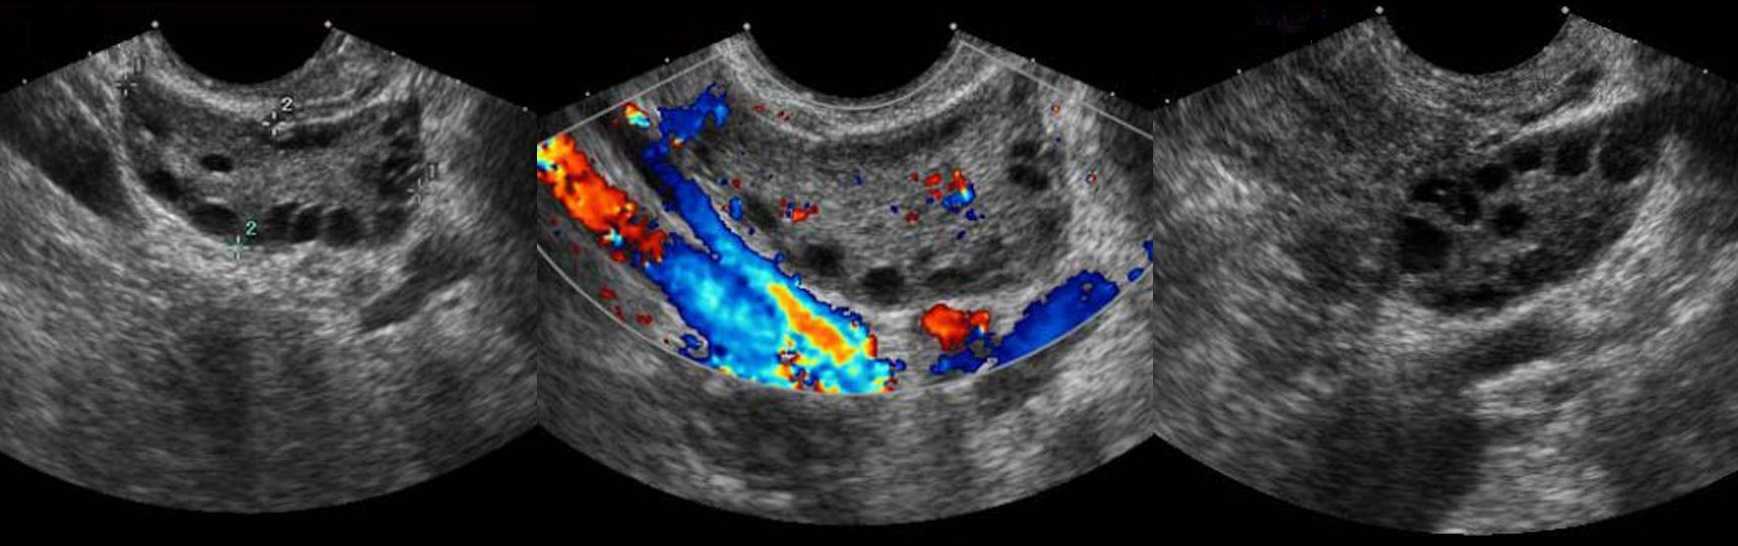

Поликистозные яичники на УЗИ

При сочетании гиперандрогении и хронической ановуляции говорят о синдроме поликистозных яичников (СПКЯ). У пациентов с СПКЯ олигоменорея, бесплодие, гирсутизм и ожирение. Требуется исключить другие причины — врожденная гиперплазия надпочечников, синдром Кушинга, андрогенсекреторная опухоль.

УЗИ критерии поликистозных яичников: процесс всегда двусторонний; яичники увеличены > 10 см³; в каждом яичнике более 25 (критерии Роттердама более 12) фолликулов; размер фолликулов от 2 до 9 мм. Другие морфологические особенности:

- наружные отделы коркового слоя склерозированы — гиперэхогенная «скорлупа»;

- центральная зона расширена, гиперэхогенная, дольчатого строения за счет фиброзно-склеротических тяжей;

- между склерозированной капсулой и мозговым веществом располагаются небольшие фолликулы, часто по типу «жемчужного ожерелья»;

- наружный слой большинства фолликулов гиперплазирован — фолликулярный гипертекоз.

Во время овуляции доминантный фолликул должен прорваться и освободить яйцеклетку. При СПКЯ патологическая «скорлупа» препятствует полноценной овуляции и наступлению беременности. Предполагают возможность подкапсульной овуляции, когда фолликулярная жидкость не покидает пределов яичника. Некоторые авторы считают термин склерокистоз яичников более точным.

При функциональных поликистозных яичниках фиброзная капсула отсутствует, объем мозгового вещества не меняется, ановуляция происходит из-за гормональных нарушений фолликулогенеза, а после гормональной коррекции наступает беременность. При СПКЯ гормонотерапия неэффективная, беременность наступает только после каутеризации яичников.

Рисунок. Пациентка с жалобами на олигоменорею и неспособность к зачатию. На УЗИ оба яичника увеличены, гиперэхогенная капсула, мозговая зона расширена, гиперэхогенная, по периферии анэхогенные округлые образования, размером 3-8 мм. Заключение: Эхо-картина может соответствовать склерокистозу (синдром поликистозных яичников).